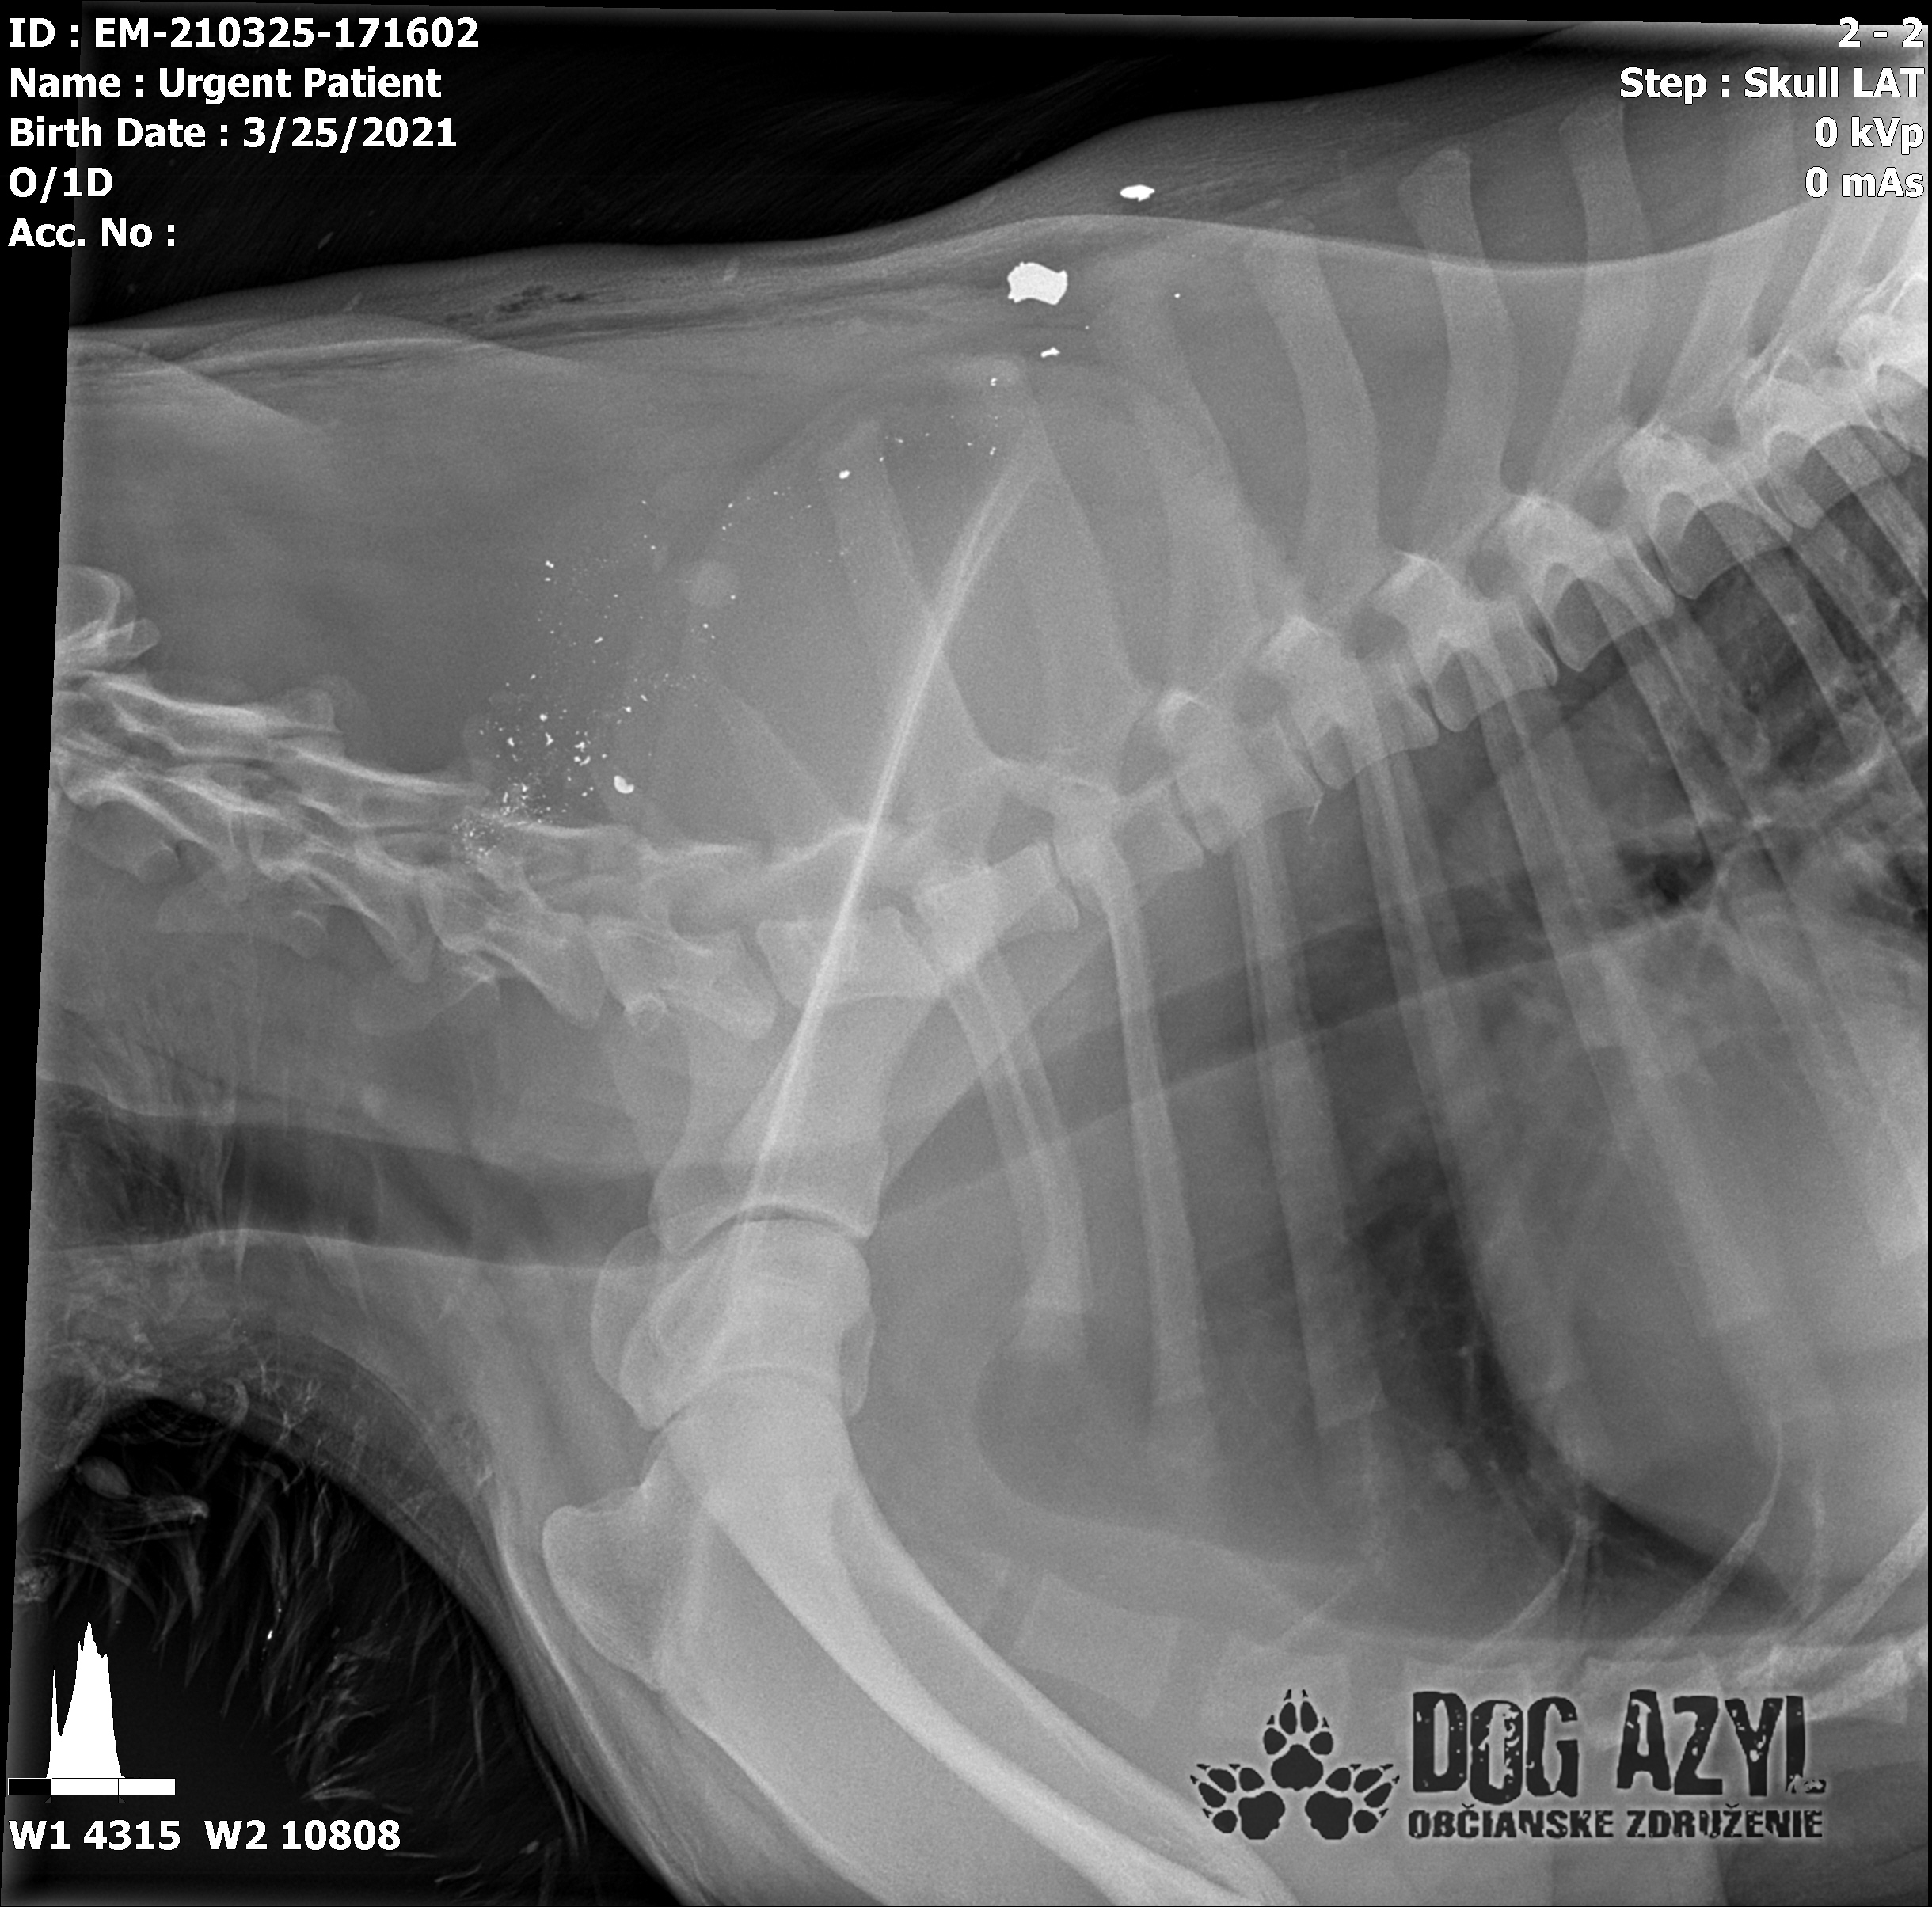

Včera bol odovzdaný do rúk najlepších špecialistov na veterinárnu kliniku Sibra centrum. Boli mu urobené všetky vyšetrenia, vrátane MRI a CT. Zistilo sa, že slabosť v jeho ľavej strane a dôvod, prečo sa nevie postaviť, je spôsobená fragmentom medzi 4. a 5. stavcom, ktorý tlačí na miechu. Padol verdikt, okamžitá operácia. Dnes už má za sebou veľmi náročnú, niekoľkohodinovú operáciu, ktorá podľa slov MVDr. Vatolíka dopadla dobre, ale v takomto stave a po takto náročnej operácii sa prognóza nedá určiť.

Strela zasiahla Barisa v oblasti lícnej kosti, ktorá mu rozdrvila sánku a následne putovala cez krk až po krčnú chrbticu. Úlomky z guľky (neviem ako sa to odborne volá) sa roztrieštili na "milión" kusov počas svojej cesty. Tieto úlomky sú všade (ako vidieť aj na RTG). Jeden (alebo niekoľko týchto úlomkov) sa dostali až po miechu, ale našťastie ju neprerazili. Toto spôsobilo, že Baris citlivosť v nohách na ľavej strane sice má, ale má poškodenú motoriku. Tieto úlomky sa z oblasti stavcov, miechy aj krku dnes odstránili, ale Barisko z ďaleka nemá vyhraté. Miecha je totiž zakrvácaná (opäť sa ospravedlňujem za nepresnosť a laickosť) a to, že ako veľmi je poškodená, alebo či jeho slabosť bola spôsobená "iba opuchom" sa ukáže cca do 24 hodín. Ak Baris nedajbože do zajtra stratí citlivosť v nohách, tak.. žiaľ... Ale! ak citlivosť zostane, prípadne nastane aj zlepšenie, tak vzplanie plamienok ďalšej nádeje a bojujeme ďalej!